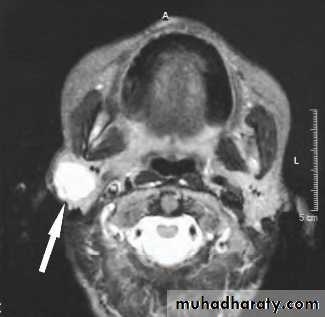

May present with multiple parotid cysts which cause gross parotid swelling and facial disfigurement.

CT&MRI; characteristic Swiss cheese appearance of multiple large cystic lesions.

The swollen glands usually painless and may regress on the institution of antiviral therapy.Cysts may be aspirated